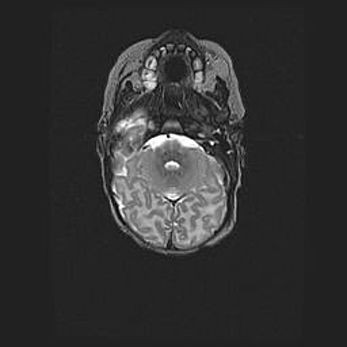

Мальформация Денди-Уокера. Киста задней черепной ямки.

Агенезия мозолистого тела.

Возраст: 2,5 месяца

Вес: 2420 г

Пол: женский

Окружность головы: 37 см

Срок гестации: 32 недели

Мальформация Денди—Уокера — редкий вид патологии ЦНС, представляющий собой врожденный порок развития каудального отдела ствола и червя мозжечка, ведущий к неполному раскрытию срединной (Мажанди) и латеральных (Лушка) апертур IV желудочка мозга. Для этогно синдрома характерна триада симптомов: гипотрофия червя мозжечка и/или полушарий мозжечка, кисты задней черепной ямки, гидроцефалия различной степени. В 70% случаев порок сочетается и с другими аномалиями головного мозга, в частности с агенезией мозолистого тела.